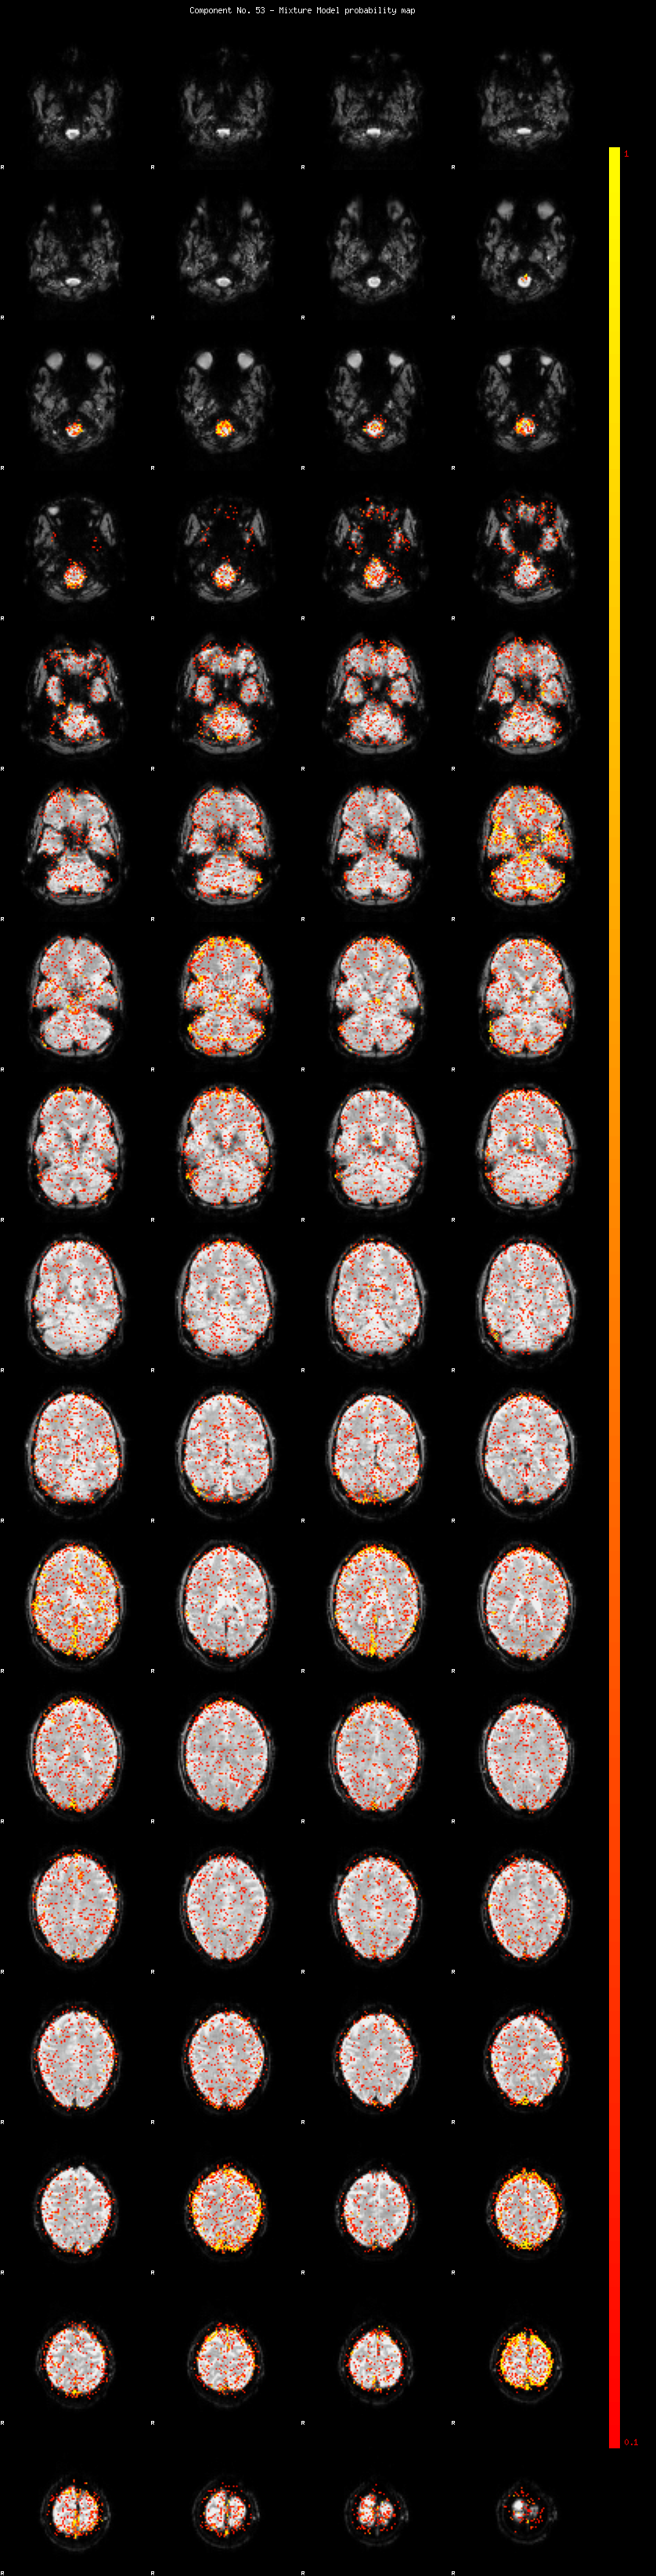

IC_53 Mixture Model fit

Means : 0.000000 2.430989 -2.231966

Vars : 1.000000 1.849518 1.262127

Prop. : 0.932262 0.033590 0.034148